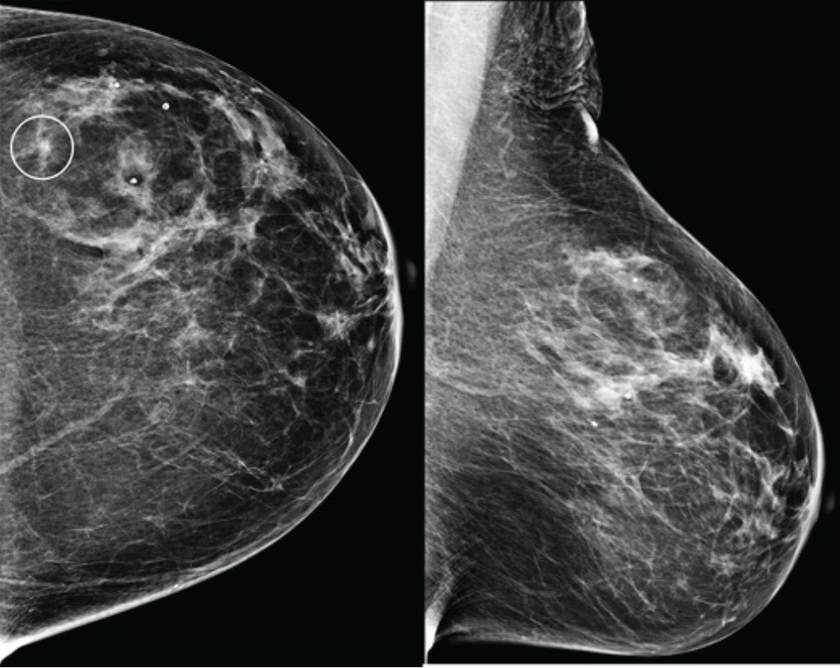

В конце августа 2025 года американский стартап Calidar представил инновационную систему 4D-маммографии, которая выводит точность диагностики злокачественных образований молочной железы на новый уровень. Эта платформа визуализации использует рентгеновскую дифракцию и искусственный интеллект для проведения исследования на молекулярном уровне.

Первая в своем роде система 4D-маммографии, разработанная компанией Calidar, позволяет решить существующие проблемы. Устройство измеряет, как рентгеновские лучи рассеиваются на молекулярном уровне: данный процесс известен как рентгеновская дифракция. Это создает уникальную структурную сигнатуру, которая отражает внутренний состав ткани молочной железы.Создатели ALT Linux – о сложной судьбе свободного ПО, роли Максута Шадаева и сделке с «Ростелекомом». Подкаст TAdviser

В отличие от традиционных рентгеновских снимков, которые основаны на форме и плотности, рентгеновская дифракция предоставляет дополнительную диагностическую информацию о том, из чего состоит ткань. Эти специфичные данные позволяют классифицировать раковые и доброкачественные образования с точностью, в четыре раза превышающей показатели традиционных систем визуализации.[1]